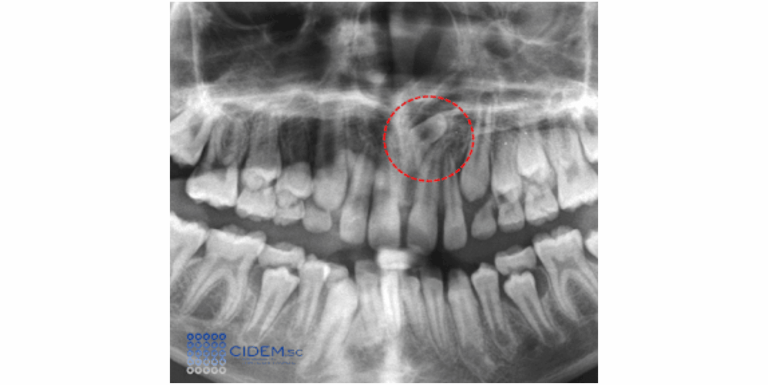

Paciente masculino con indicación de estudio mediante tomografía de haz cónico (TCHC) por presentar dolor en la unidad dentaria 23 y aumento de volumen en la zona. En la radiografía panorámica previa, se observó la anomalía de forma en la porción radicular. En vistas trasaxiales (Figura 1) y  coronales (Figura 2) se pudo constatar la invaginación del esmalte, que se extendía desde la cara palatina de la corona hacia el tercio medio radicular y se orienta a vestibular causando una aparente bifurcación del conducto radicular y compresión de la cámara pulpar.

Figura 1. Vistas transaxiales de tomografía computariza de haz cónico, donde se evidencia Dens Invaginatus en la unidad dentaria 23, que se extiende desde la palatina de la corona hacia el tercio medio radicular, el cual protruye en la tabla vestibular y causa  su adelgazamiento y expansión.

Figura 2. Vistas coronales de tomografía computariza de haz cónico, donde se evidencia en el diente 23, zona hipodensa central con aparente bifurcación del canal radicular, ápice en formación e imagen hipodensa difusa asociada al mismo, sugestiva de proceso osteolítico.

El tercio cervical del contorno vestibular del diente protruye en la tabla ósea vestibular causando su expansión y adelgazamiento. El ápice se observa en formación, sin embargo, puede evidenciarse una imagen hipodensa difusa asociada al mismo, sugestiva de lesión periapical. Las reconstrucciones volumétricas en 3D ilustran el caso (Figura 3). La imagen mostraba signos tomográficos de Dens Invaginatus (DI) tipo III.